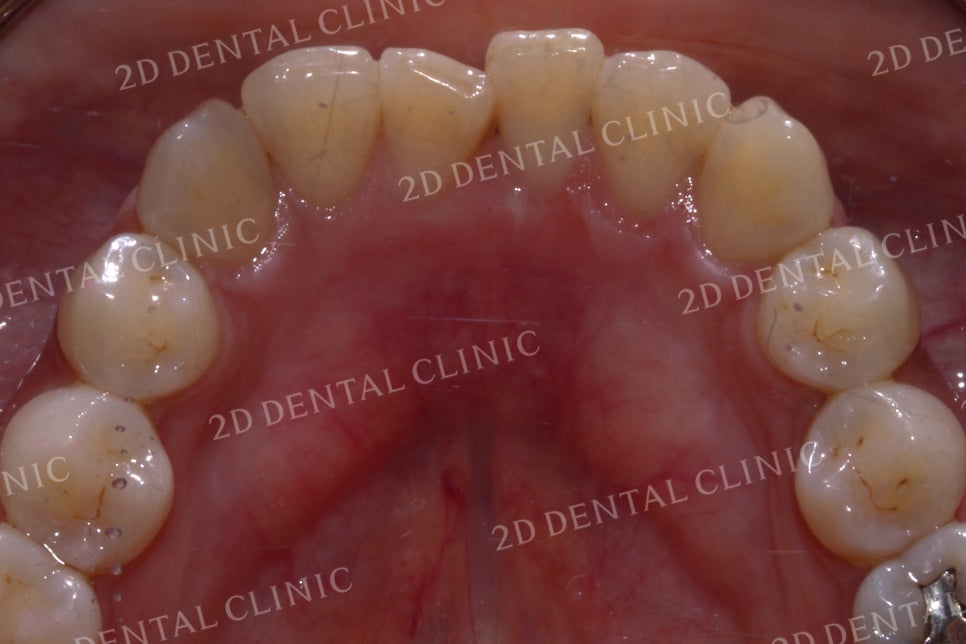

하악의 설측면 사진입니다.

전치부를 보시면

총생으로 인해 치열이

고르지 않고 삐뚤삐뚤한 모습인데요,

중절치가 틀어져 있기 때문에

정면에서 본다면 상악과 정중선이

하악의 설측면 또한 크라우딩으로

들쭉날쭉하게 배열되었던

전치부의 치아들이

가지런하게 재배열되면서

틀어져 있던 정중선도

바르게 교정된 모습입니다.